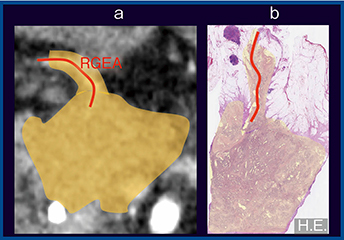

図3は,50歳代,女性の浸潤性膵管がんで,前方浸潤・神経叢浸潤を伴っている。Aquilion Precisionの拡大画像(図3 a)と術後の病理像(図3 b)を対比すると,腫瘍の浸潤範囲が良好に相関している。また,狭小化した右胃大網動脈(RGEA)の神経叢浸潤も描出されている。Aquilion Precisionでは分解能が向上したことで正常な神経叢も見えるようになったため,今後は病的な神経叢との鑑別が課題となる。

図3 症例2:浸潤性膵管がん,前方浸潤・神経叢浸潤(+)(50歳代,女性)

a:Aquilion Precision(1mm) b:病理像(H.E.)